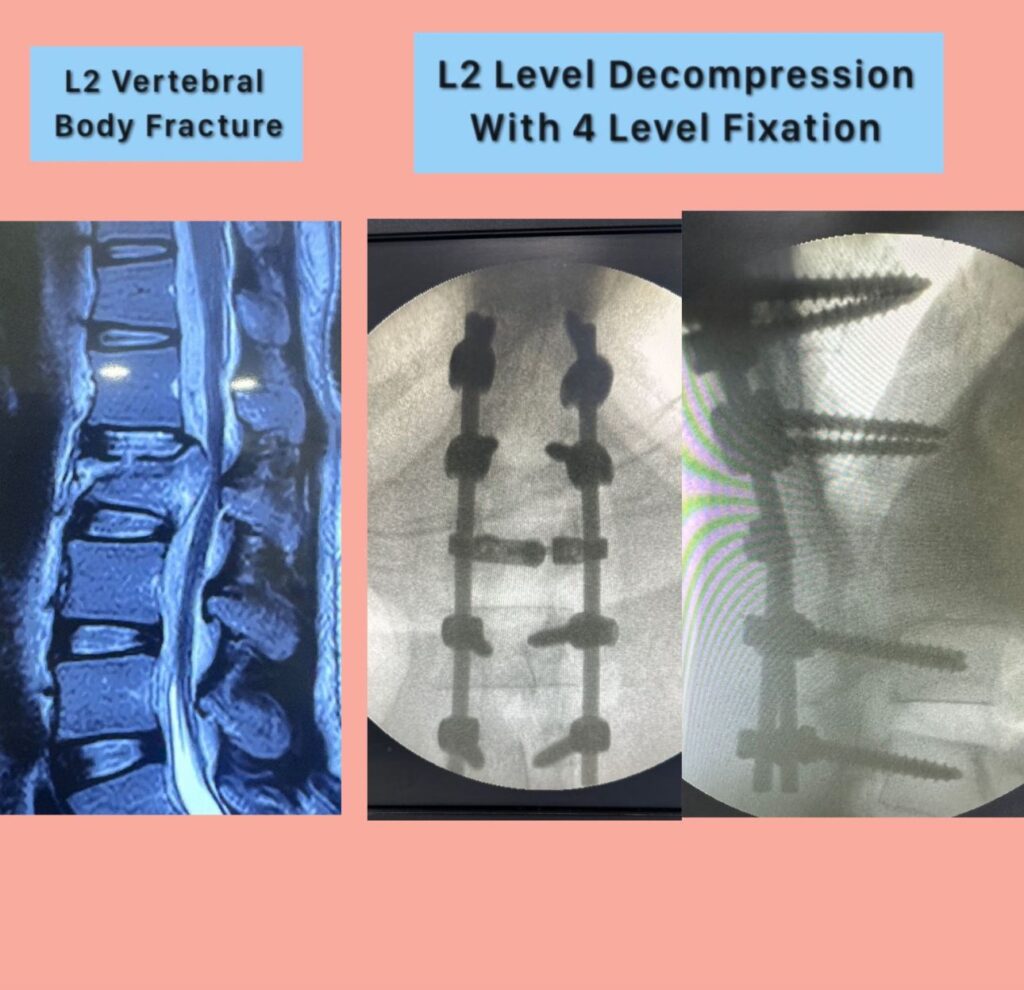

He specializes in back pain, slip disc, sciatica, and complex spine and brain disorders, with a strong focus on conservative treatment, minimally invasive surgery, and ethical, patient-centered care.